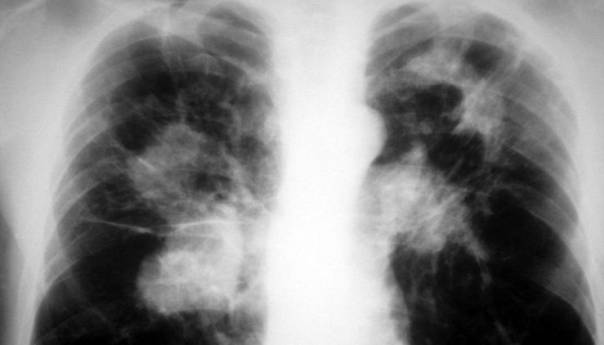

Tuberkuloza (TB) je zarazna bolest uzrokovana lako savijenim, tankim, aerobnim, nepokretnim, štapićastim uzročnikom, koji ne stvara spore, a pripada porodici Mycobacteriaceae. Od svih patogenih vrsta, koje pripadaju Mycobacterium tuberculosis (M. TB) kompleksu, najčešći i najznačajniji uzročnik bolesti kod ljudi je M. tuberculosis. Bolest može zahvatiti bilo koji organ, ali je najčešća lokalizacija u plućima.

Kada osoba oboli od tuberkuloze glavni simptomi su hronični kašalj, subfebrilne temperature, noćno znojenje, gubitak na težini, gubitak apetita, ponekad bol u prsima, a može se javiti i krvav iskašljaj.